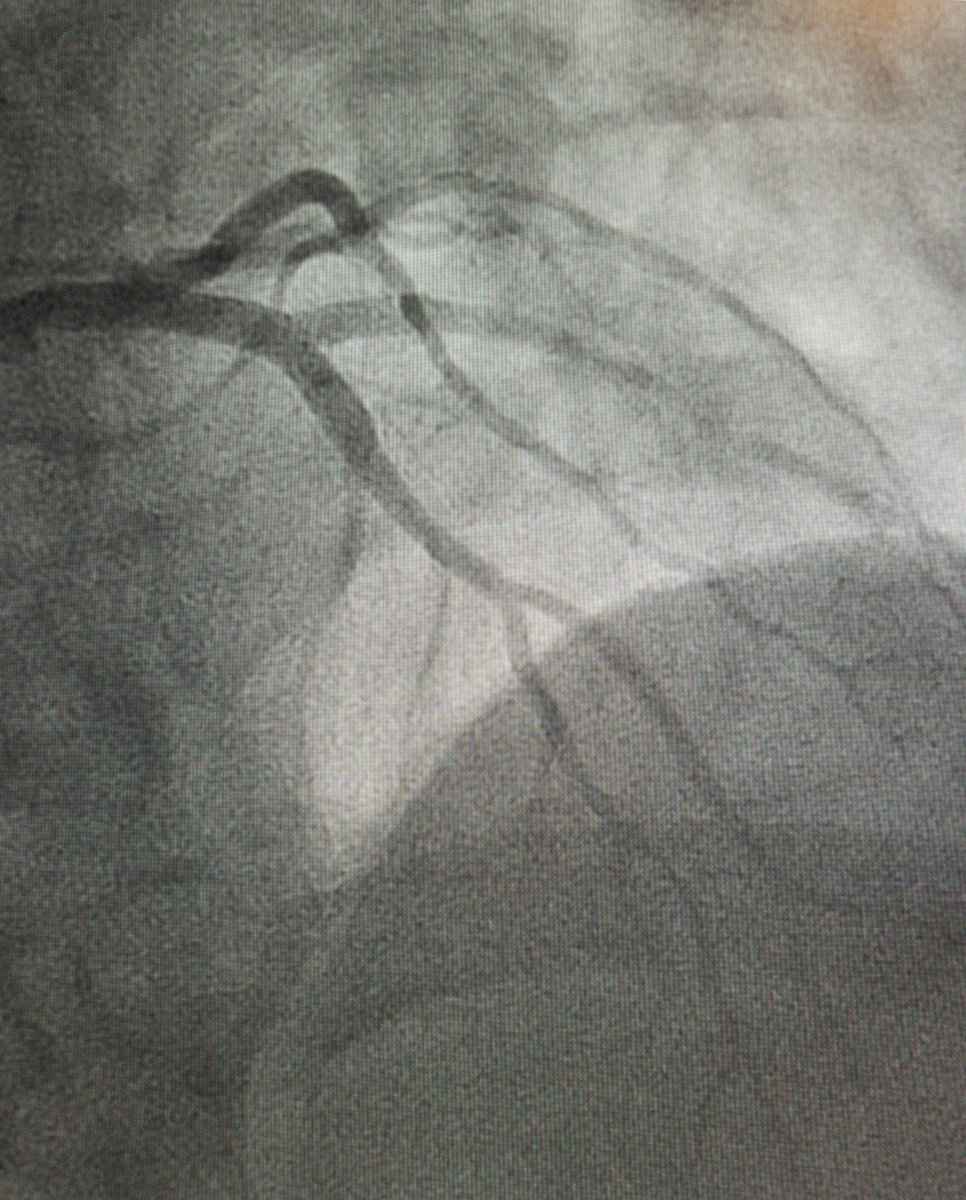

Evolution of IC Training: 2023 ACC/AHA/SCAI Advanced Training Statement on Interventional Cardiology (Coronary, Peripheral Vascular and Structural Heart Interventions): A Report of the ACC Competency Management Committee @ACCinTouch @SCAI @American_Heart ahajrnls.org/3Z4n9Dz